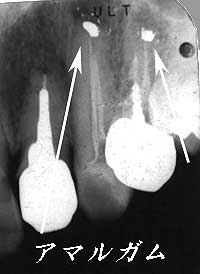

不十分な根管充填と根尖部のアマルガムが問題

根充材の一部とアマルガムが病巣内に残存

根尖部に存在する全ての異物を除去

| 【初診時】 不十分な根管充填と根尖部のアマルガムが問題 |

【根管治療後】 根充材の一部とアマルガムが病巣内に残存 |

【根尖部掻爬後】 根尖部に存在する全ての異物を除去 |